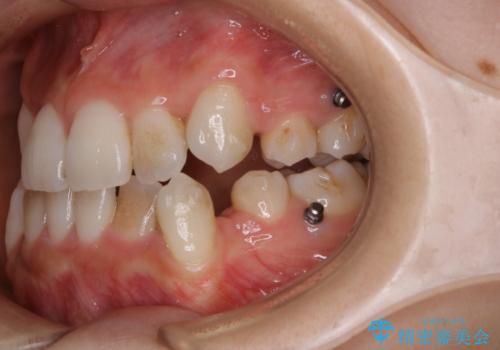

- インビザラインでのマウスピース矯正中に着色が気になるとのことでした。着色が全体的に付着していたためPMTC60分コースを行いました。

PMTC(保険外治療)は、毎日の歯磨きで落としきれない汚れや、コーヒ、紅茶・タバコのヤニなどの着色も除去します。目には見えない歯と歯の間・歯肉の境目・インビザライン中はアタッチメント周囲などに残っているプラーク(歯垢)もしっかり取り除きます。PMTCでは専門的な機械や材料を使用して、徹底的に汚れを除去するため、虫歯・歯周病・口臭予防などにつながります。